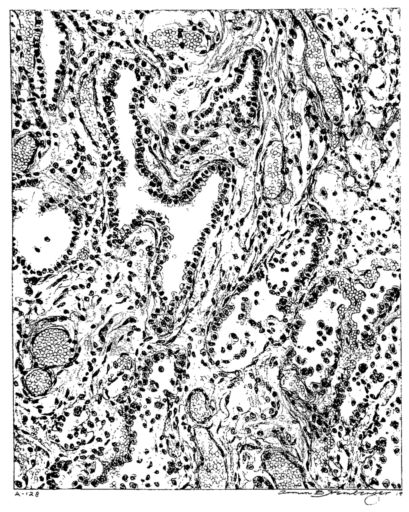

FIG. III. AUTOPSY NO. 90. DRAWING FROM A LESION OF THE TRACHEA (SOMEWHAT OLDER THAN THAT ILLUSTRATED IN FIGURE II). THE MUCOSA IS ENTIRELY LACKING. CONGESTION AND EDEMA ARE THE STRIKING FEATURES IN THE SUBMUCOSA. THE NECROTIZING PROCESS HAS EXTENDED INTO THE MUCUS GLANDS. THIS IS SHOWN IN THE LOWER PICTURE.

The changes are less marked, perhaps, in the trachea than in its finer ramifications. The mucosa is constantly more or less destroyed and large areas, usually focal, are entirely devoid of their epithelial covering. This is replaced by a sparse exudate, composed largely of red blood cells, mucus, a small amount of fibrin, and nuclear fragments (Fig. II). It may dip into the submucosa for a short distance, but usually these indentures are associated with the ducts of the mucous glands into which the inflammatory reaction extends. A more striking feature than the exudate, however, is the edema and the congestion of the submucosa. The loose areolar tissue of the submucosa is spread widely apart, and throughout it distended blood vessels are very conspicuous. Occasionally such a vessel is broken and actual hemorrhage appears in the submucosa. Occasionally, too, the inflammation extends down the duct to the mucous gland itself, and here, also, aplastic inflammatory reaction is evident, inasmuch as the acini now stain intensely red with the cells undifferentiated from each other and specked here and there by broken remains of the dead nuclei (Fig. III). After the disease has continued for a short period, even at the end of five or six days, some regeneration of the epithelial lining may be seen (3) (Fig. IV). But despite this, the acute picture persists, and there goes on, side by side, an attempted repair characterized by epithelial regeneration and the same evidence of acute change. Since the lesion is essentially a superficial one, scars or contractures of any extent are not encountered in the trachea, even in examples of the disease that have ended fatally only after many weeks.[4]